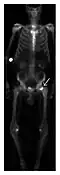

The most traditional method is bone scintigraphy. Although scintigraphy is highly sensitive for the detection of occult fracture, its lack of specificity limits its diagnostic utility. However, when MRI is not available, scintigraphy may be of value, especially in the absence of trauma history, for example, for detection of insufficiency and fatigue fractures. While radiography may show only late signs of bone reaction (such as periosteal thickening and band of sclerosis), scintigraphic examination allows for earlier detection of bony changes. Regarding Fluorine-18 2-deoxy-D-glucose (FDG) positron emission tomography (PET), it is critical to be aware that occult fractures may be responsible of marked metabolic uptake, and, thus, represent a potential false positive of metastatic disease. Integrated hybrid single-photon emission computerized tomography (SPECT)/CT combines the detection of abnormal bone metabolism with SPECT, to the precise anatomical detail provided by high resolution CT. For instance, SPECT/CT may be interesting in the detection of radiographic occult fractures of the wrist and other sport-related injuries.[1]

Proximal femoral fractures usually occur in osteoporotic patients, and their signs include subtle neck angulation, trabecular angulation, and subcapital impaction line. A frog-leg lateral view may be helpful if the greater trochanter is short enough. However, positioning can be difficult because of hip pain. In patients with strong suspicion of proximal femoral fracture and negative radiographs, MRI limited to coronal T1 W images and scintigraphy can be highly valuable (Figures 13 and 14). Such an option, with limited examination time, is cost-effective and allows reliable exclusion or confirmation of the diagnosis, preventing an unnecessary stay at the hospital or delayed treatment. Moreover, MRI helps to detect soft tissue abnormalities which are more frequently seen in femoral, acetabular, and pubic injuries than sacral lesions. Concomitant fractures are also frequently seen in typical pelvic sites.[1]

Figure 14: Subcapital insufficiency fracture in a 55-year-old man with a left hip pain without a history of trauma. Anteroposterior and Lauenstein view radiographs centered on the left hip do not show an obvious fracture line, but mild acetabular osteophytosis was noted consistent with hip osteoarthritis (not shown). (a) Coronal T1-weighted MRI shows a linear low-signal band through the femoral neck corresponding to a fracture line (arrowheads). (b) Bone scintigraphy shows focal uptake (arrow) corresponding to the fracture.[1]